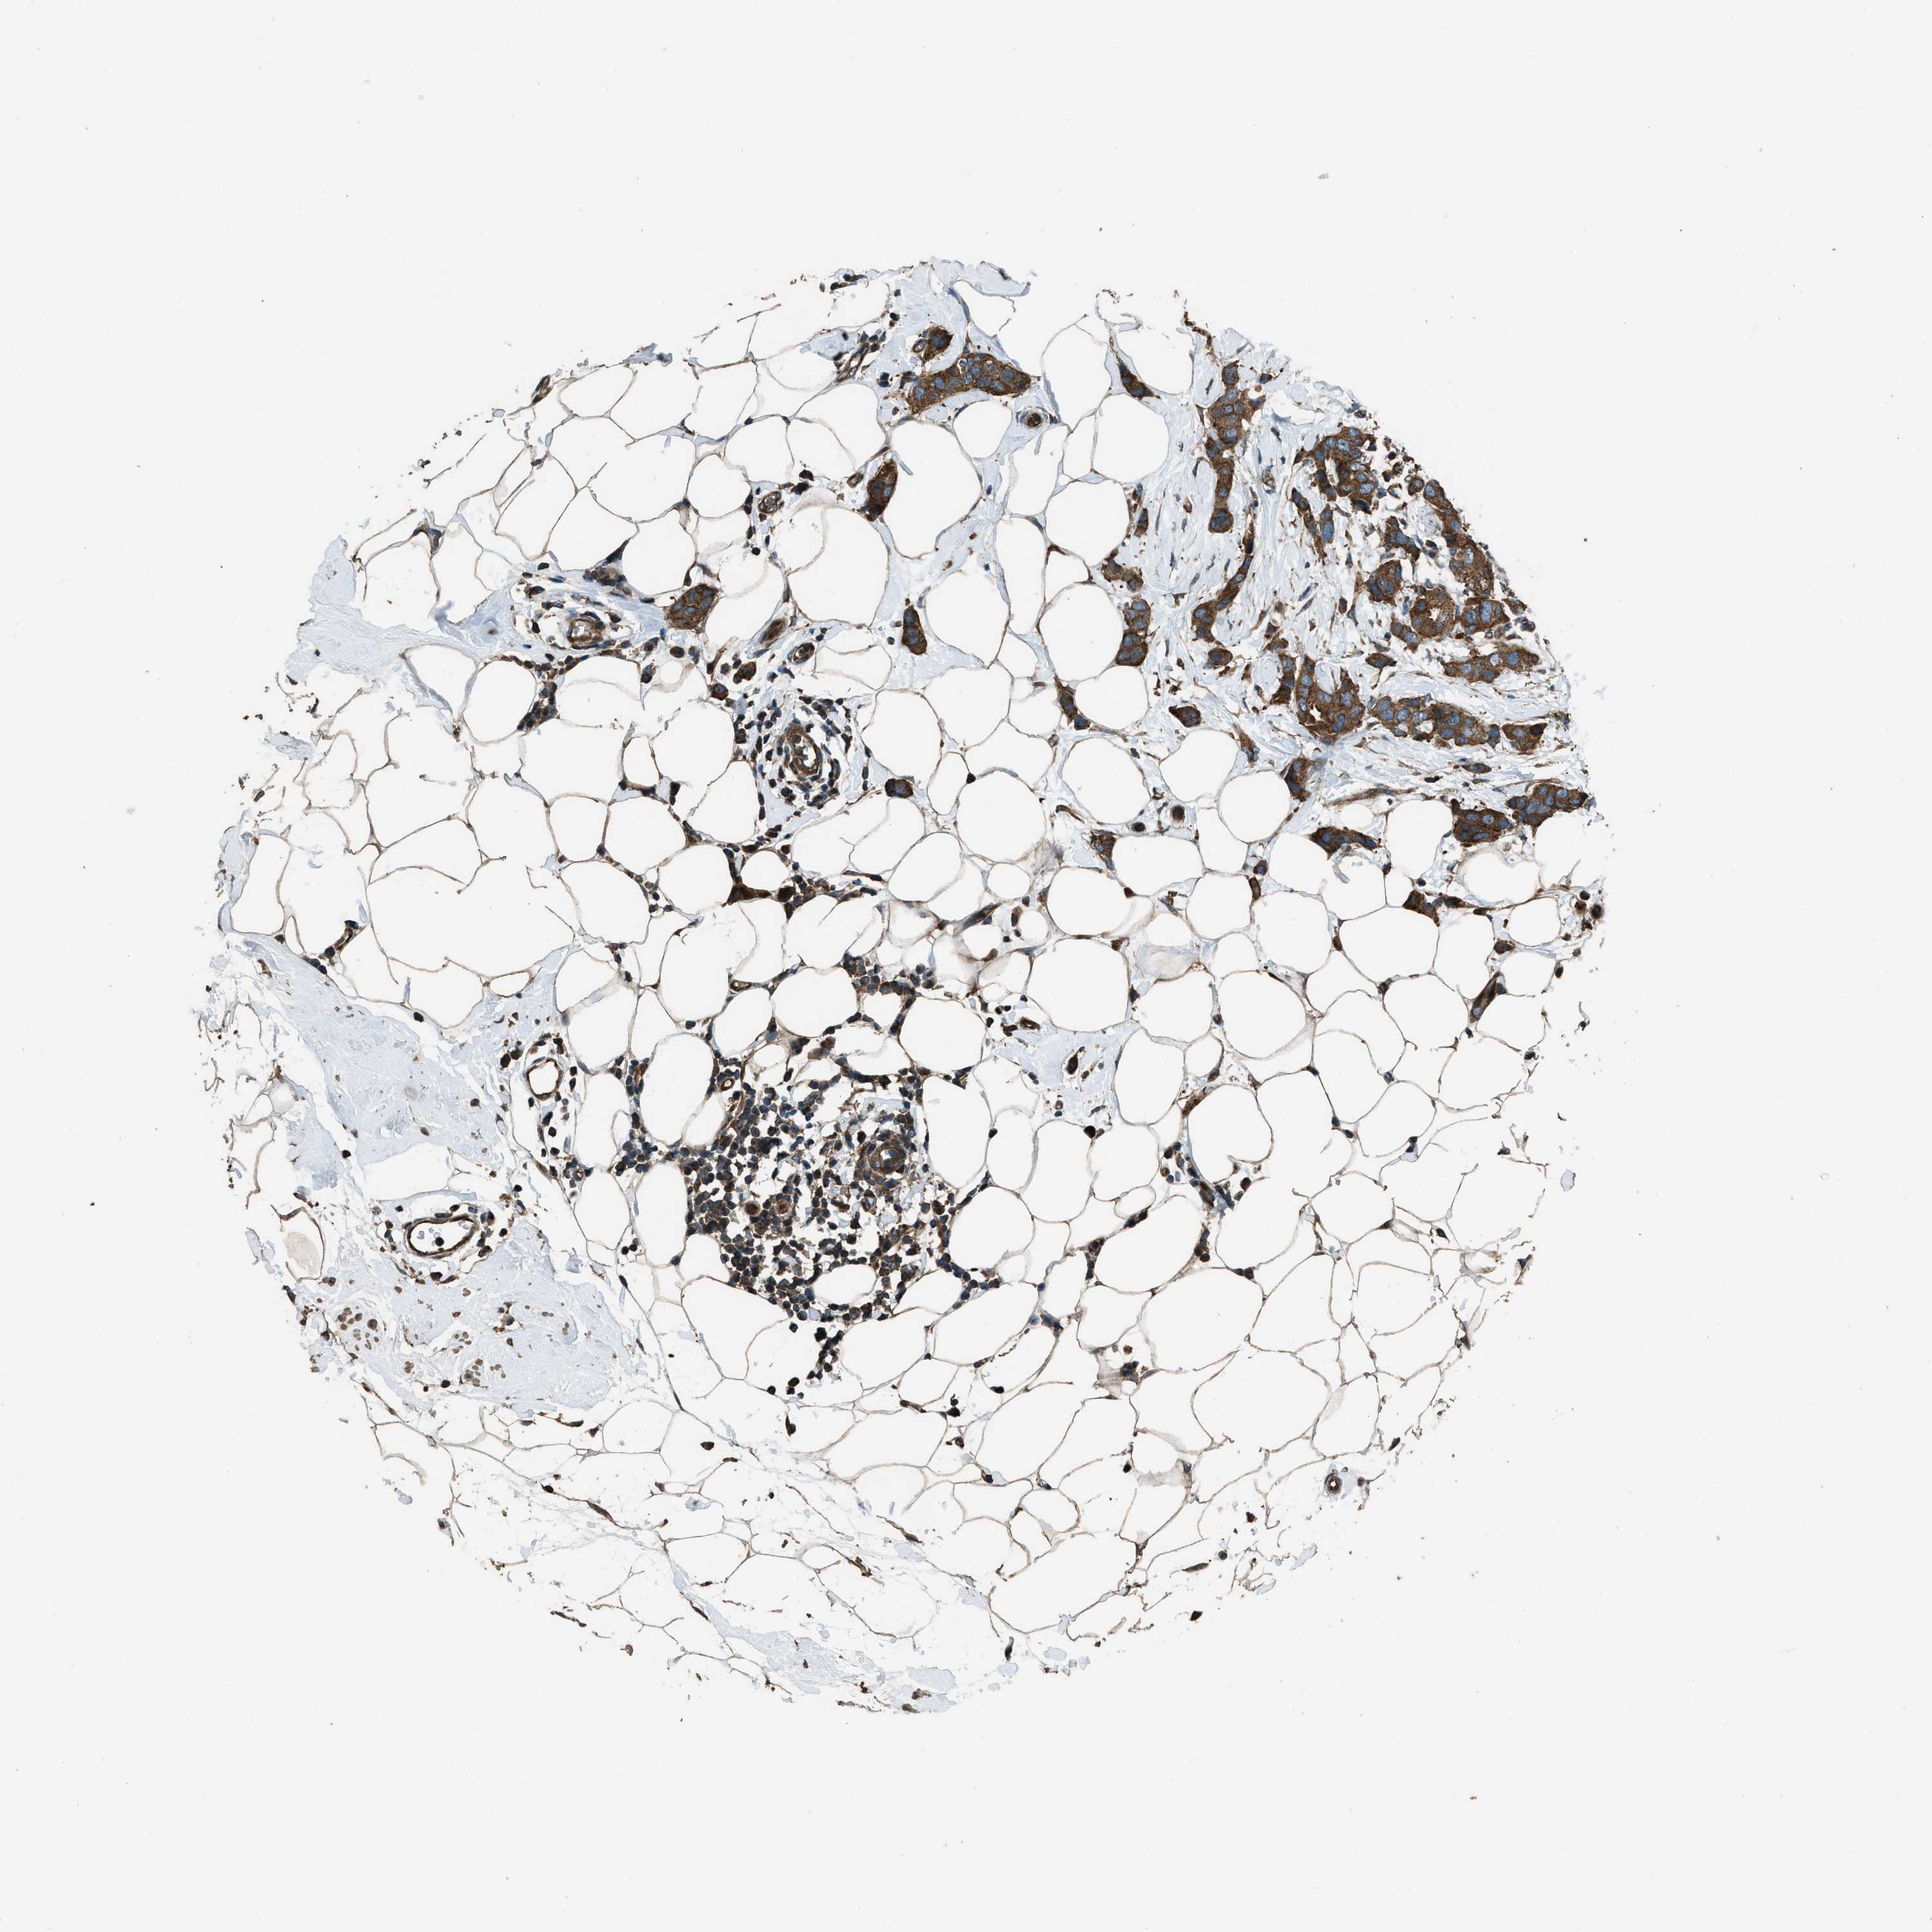

CANCER BREAST CANCER Show tissue menu

BRCA TCGA BRCA VALIDATION PROTEIN EXPRESSION